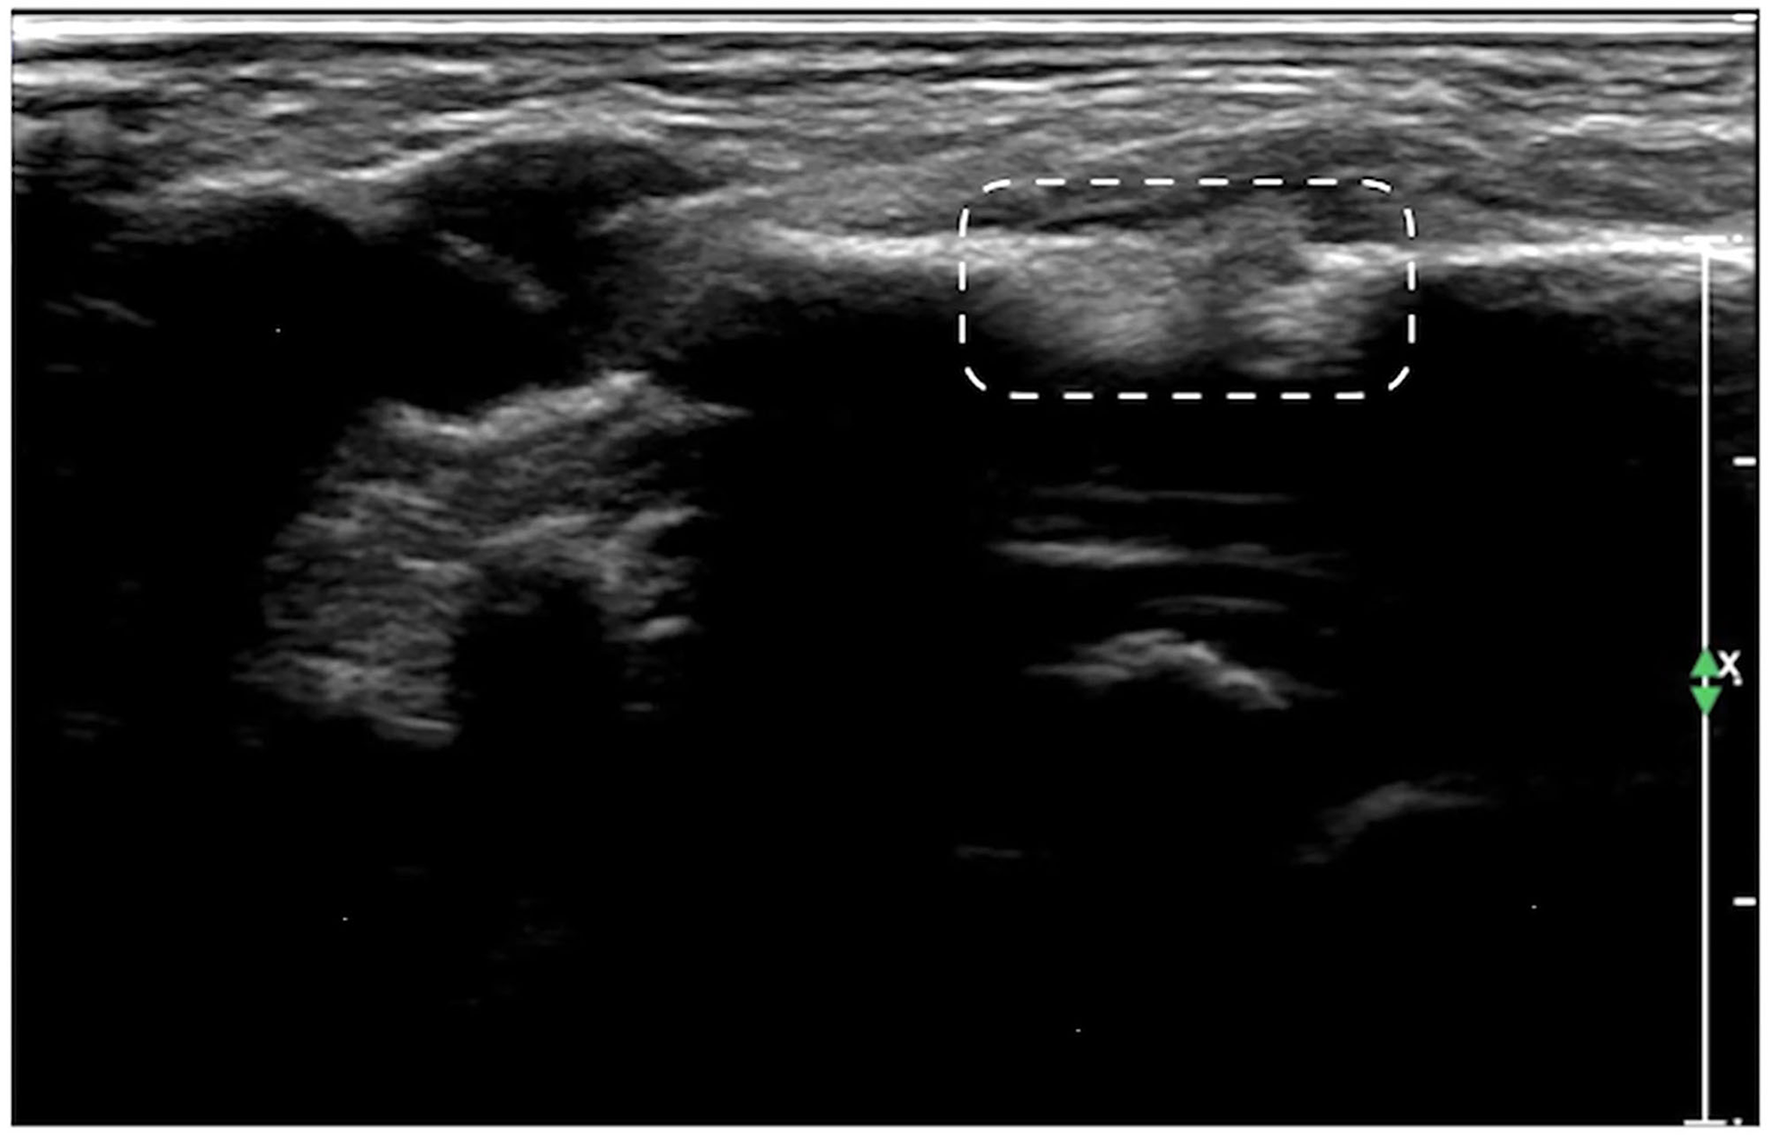

Figure 7

Callus formation. The infant was G1P1, with a gestational age of 39+5 weeks, vaginal delivery, and a birth weight of 3,700 g. The infant was admitted to the hospital on the 7th day after birth due to jaundice. Physical examination revealed local swelling and callus formation on the medial segment of the right clavicle. Ultrasound examination showed interrupted continuity and local bone tissue proliferation forming a callus at this fracture site (within the dashed line).